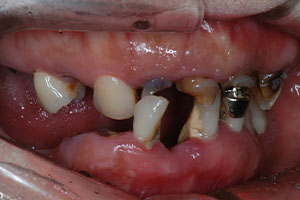

치료증례 전후사진

Before & After